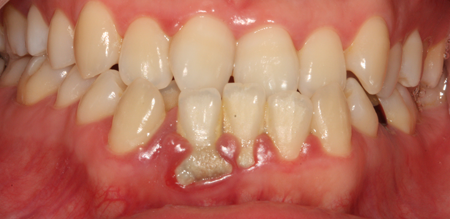

치주치료

청담네오플란트는 치주치료를 통하여 치아를 살릴 수 있는 기회를 놓치지 않습니다.

치주염(잇몸병)은 치아에 붙어있는 치석 및 세균 등에 의한 염증반응으로 잇몸뼈가 상실되는 질환을 말합니다.

초기에는 잇몸이 붓거나 잇몸에서 피가 나는 증상이 나타나며 계속 방치하면 치아를 발치해야 할 수도 있습니다.

치주치료는 이러한 치석 및 세균 등을 제거하여 잇몸뼈를 안정된 상태로 유지하는 시술을 말하며, 청담네오플란트에서는 치의학박사 / 전문의가 직접 시술하고 있습니다.

치주치료 전후사진